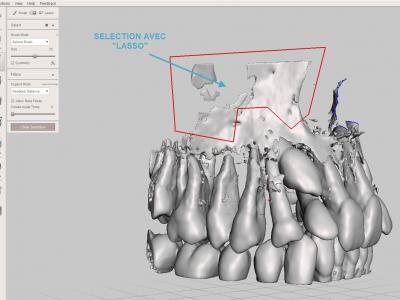

Sélectionner une zone complète à éliminer avec l'outil "Select" "Lasso", puis les supprimer avec le raccourci clavier "X"